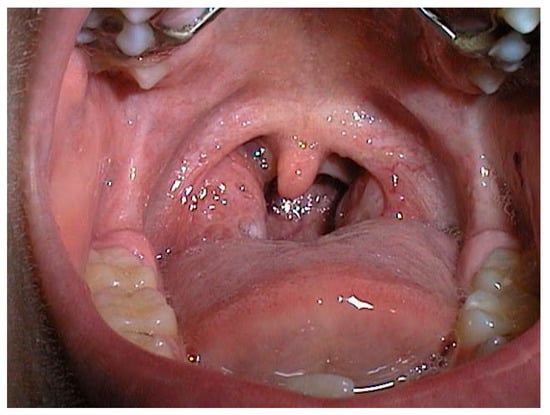

| Grade | Description |

|---|---|

| 0 | No tonsils seen |

| I | In tonsillar fossa |

| II | Visible beyond anterior pillars |

| III | Extended ¾ of way to midline |

| IV | Completely obstructing airway (kissing tonsils) |